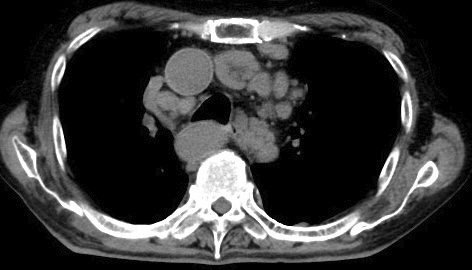

甲氨蝶呤相关的霍奇金淋巴瘤在甲氨蝶呤起始治疗几十年后发生。

Methotrexate-associated Hodgkin Lymphoma Occurring Decades after Methotrexate Initiation.